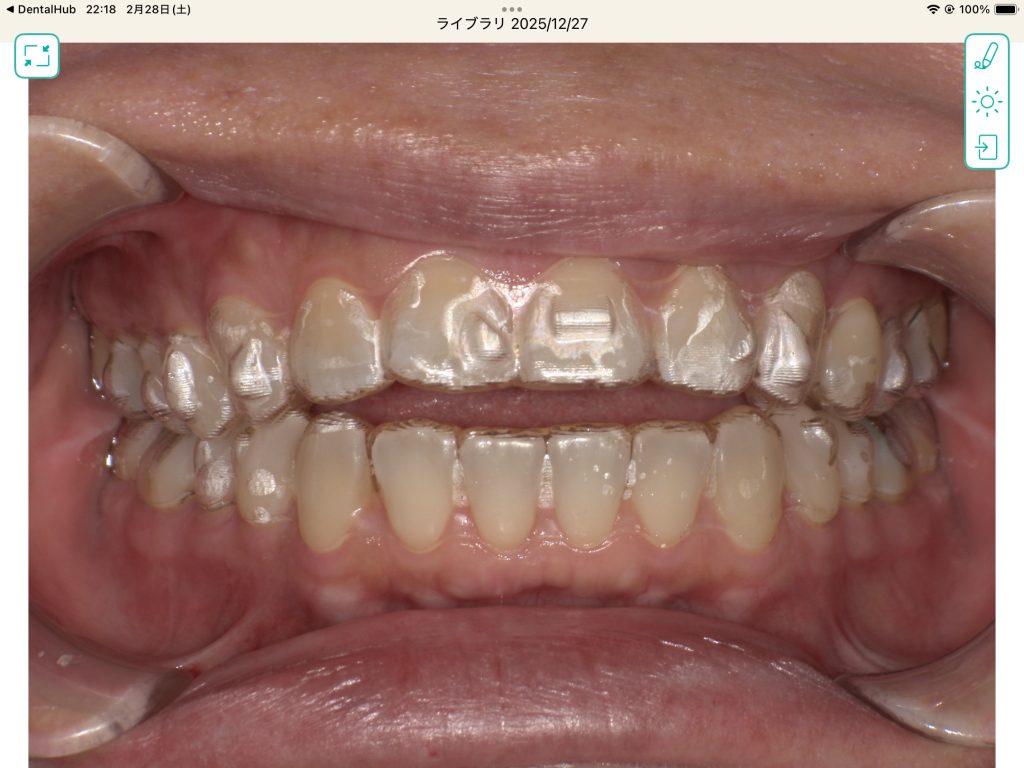

開咬改善

まだ矯正途中ですが、2ヶ月で開咬を改善出来ました。(矯正担当は村本先生)

従来型のブラケット矯正(ワイヤー矯正)では短期改善は難しい症例と思います。

マウスピース矯正ならではの改善症例と思います。